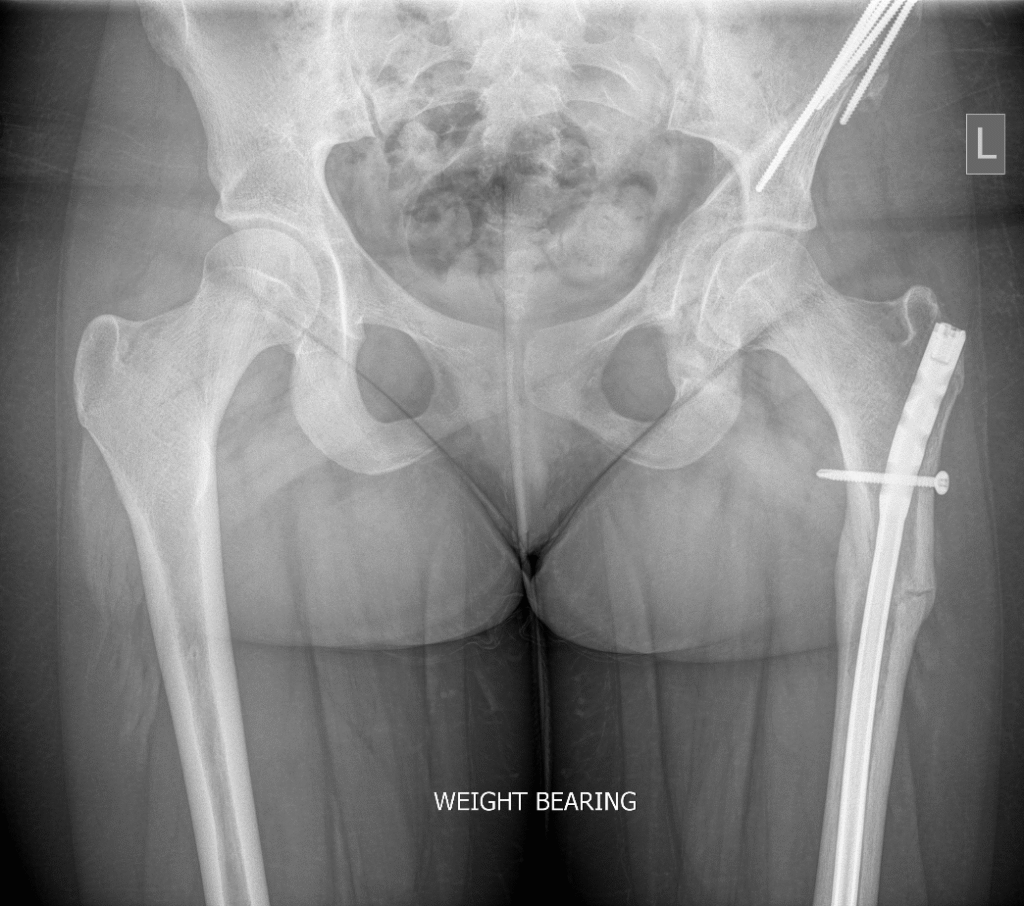

Example of Femoral Ostoeotomy

A partially united femoral osteotomy with intramedullary nail below a periacetabular osteotomy